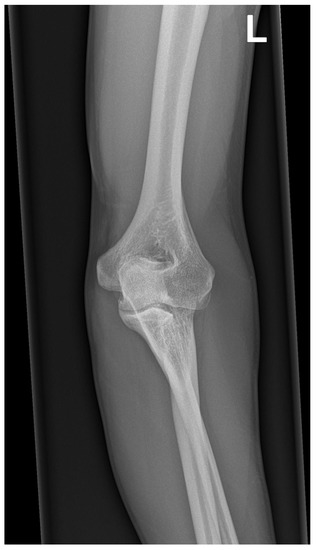

2.2. Radiographic Evaluation